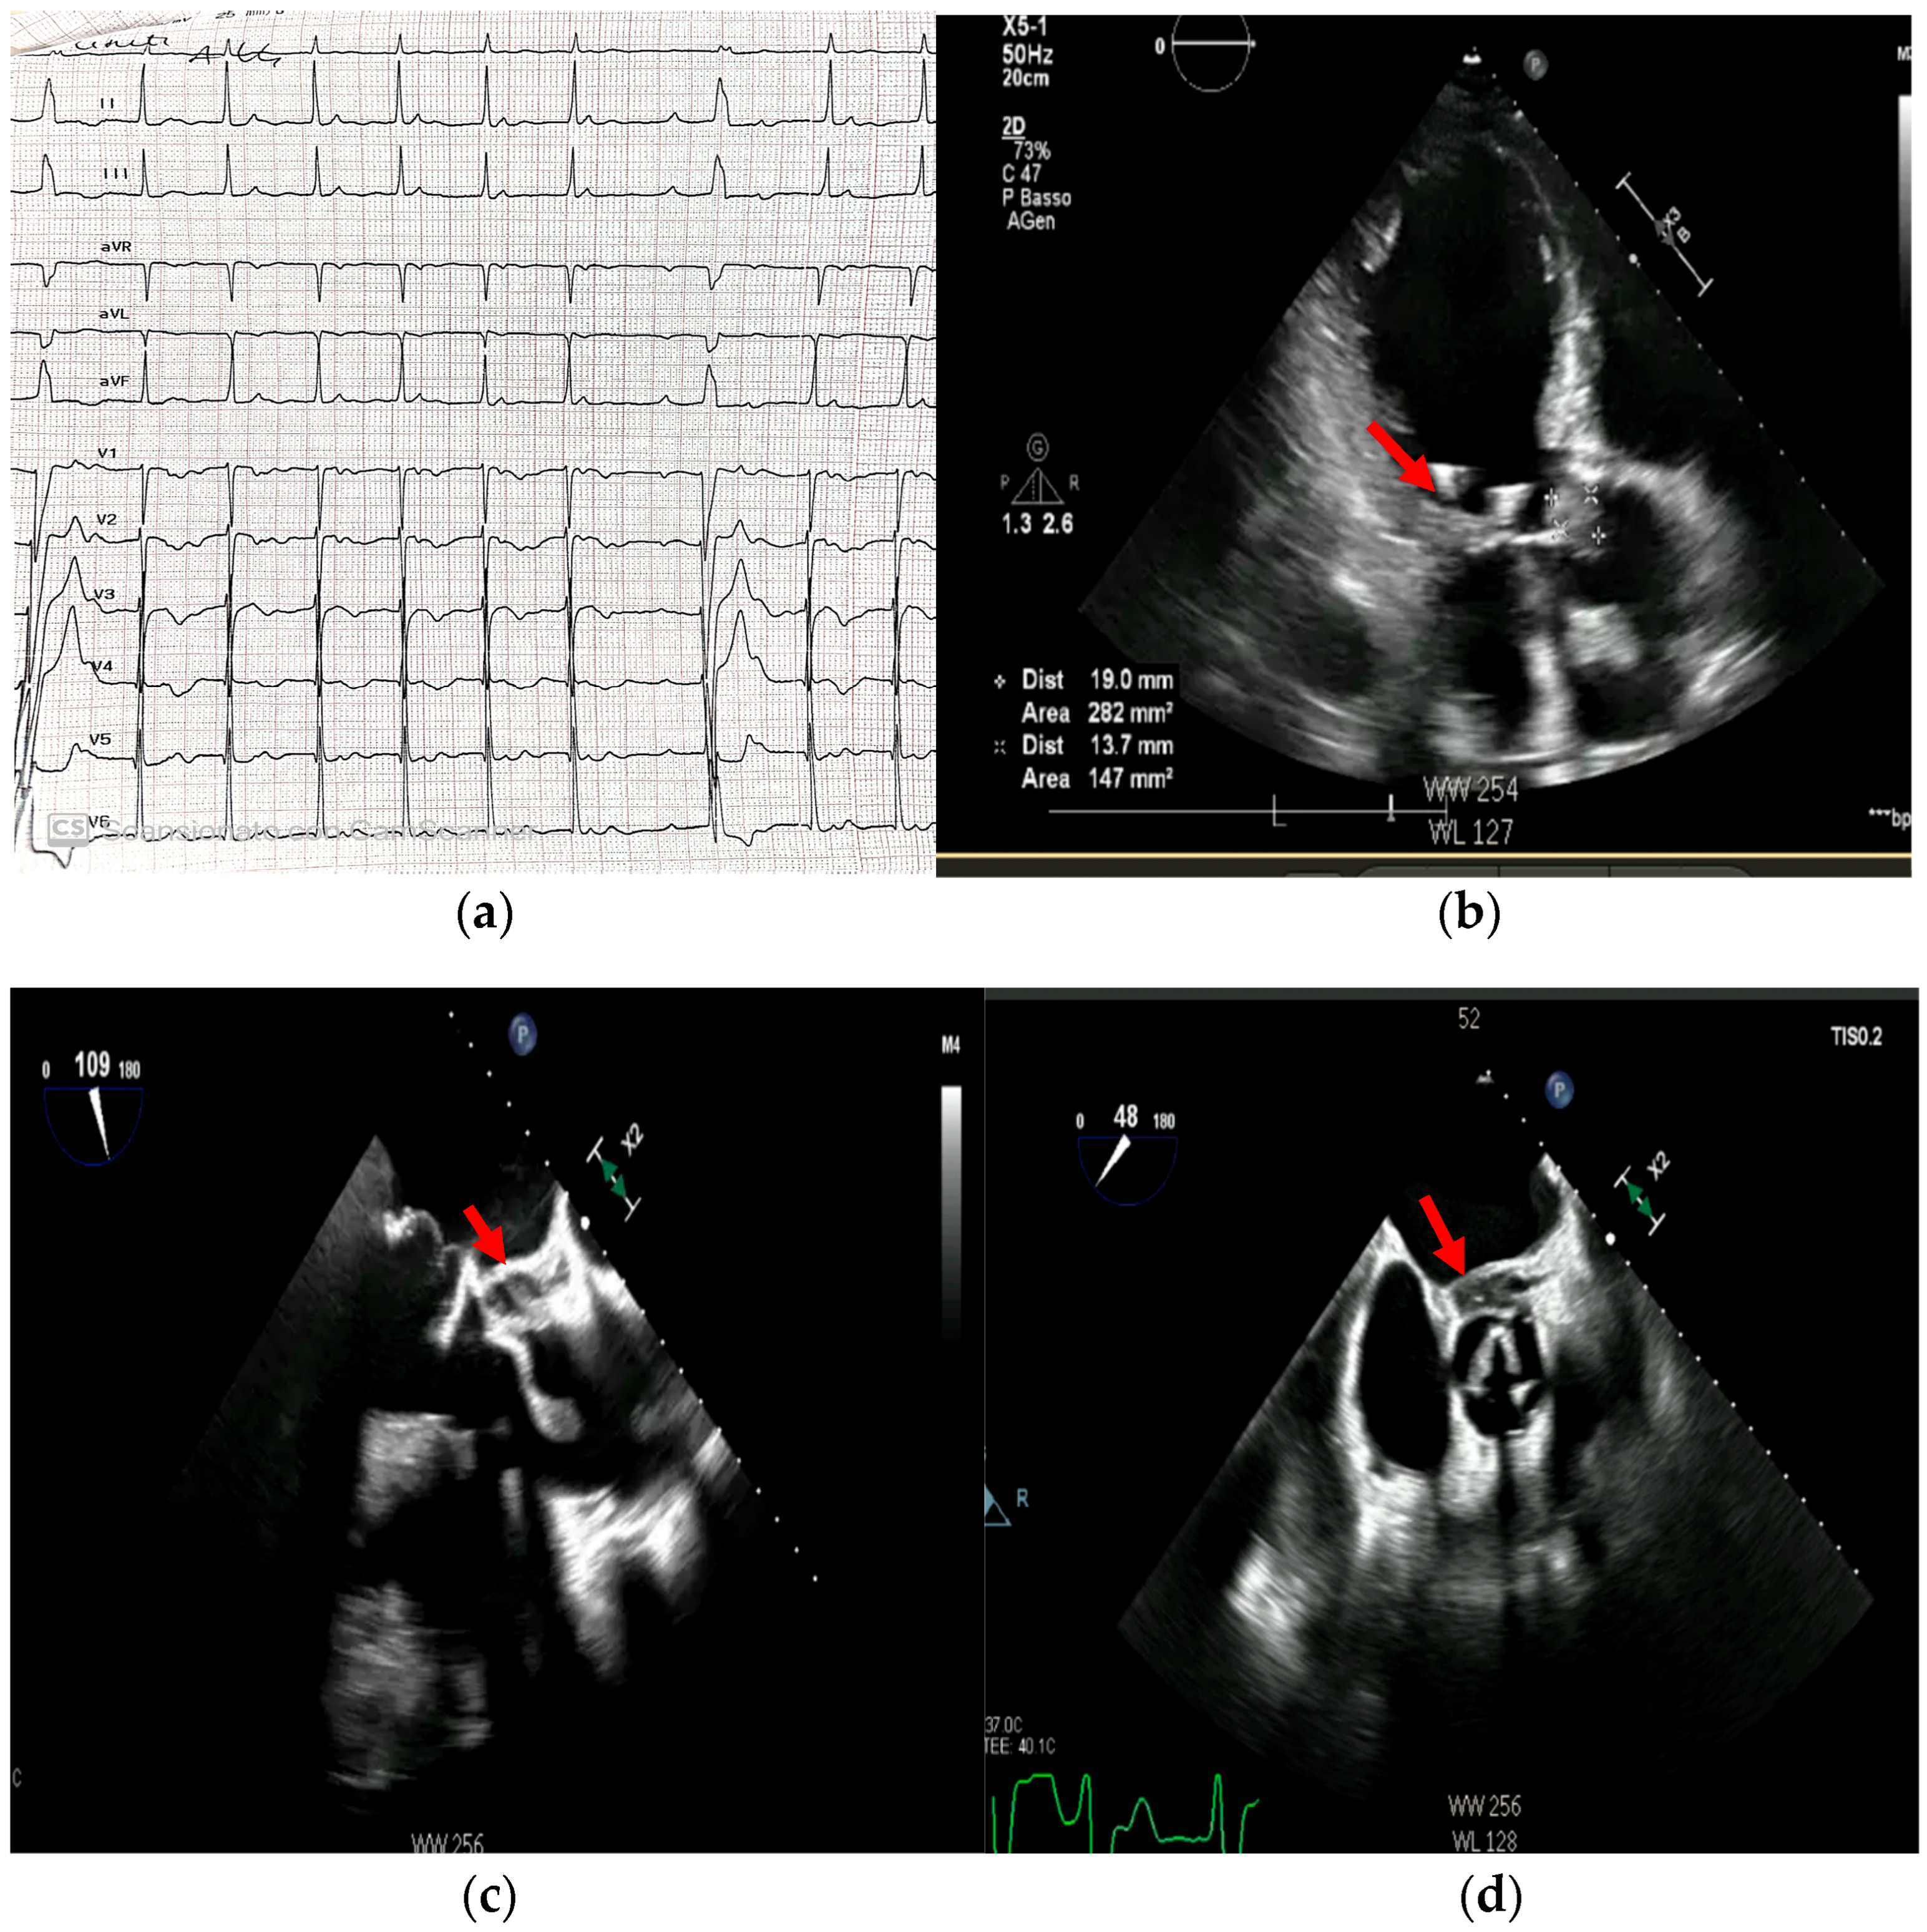

4. Echocardiography

- Echocardiography: As the cornerstone of diagnosis, echocardiography’s limitations in the setting of prosthetic material and operator dependence are well-known. The presence of sewing ring and stent frame shadowing can obscure critical findings, and Doppler flow malalignment may lead to underestimation of prosthetic valve gradients and regurgitation severity [37,58].